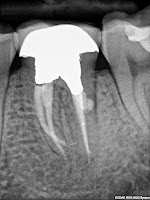

This patient presented with severe pain.

Root canal retreatment was initiated on tooth number 30. Her symptoms disappeared after the first visit, after locating and instrumenting the missed DL canal. There was also a Middle Mesial canal.

Interestingly, the final radiograph doesn't look that different.